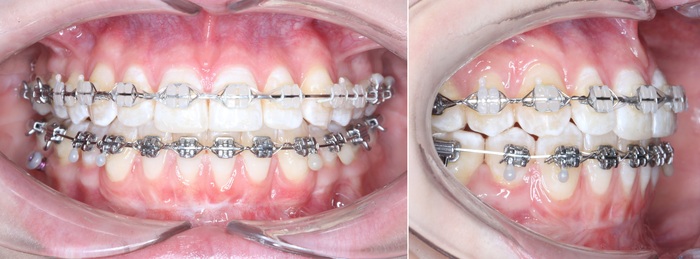

Далее проведена пластика десны, снова два месяца ожиданий и установка временной коронки:

Ну, такое, согласен, но это начало.

Еще через пару месяцев временную коронку сняли для изготовления новой:

И вот картинка спустя полгода «ношения» новой временной коронки: